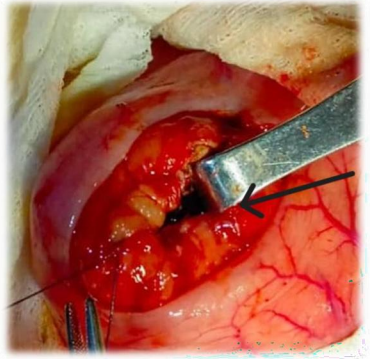

Findings: Large pancreatic pseudocyst rejecting the stomach upwards located at the lesser sac but with the maximum projection at the transverse mesocolon. Wall thickness: 7mm, smooth, no solid areas or nodularity. About 1.5L of clear yellowish fluid drained. Sample of the fluid collected for: Amylase levels, cytology and MCS.

Procedure: Exploratory Laparotomy using a Hanrahan incision, a Transmesocolic Pseudocysto- Jejunostomy in 1 layer of Vicryl 2.0 was performed.

Figure 3